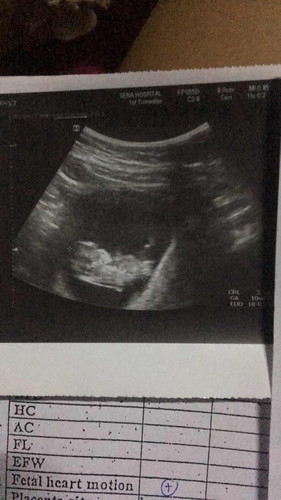

ท้องแรกคะแต่ท้องไม่ออกกังวลคะกลัวลูกตัวเล็กท้องไม่ตึงแต่ท้องนิ่ม แต่ไปตรวจมาก็เห็นหัวใจลูกนะคะหมอบอกเต้นปกติ แต่ก็ยังงงๆท้องไม่ออก

เพิ่งจะ 10 สัปดาห์เองค่ะ ทารกขนาดยาวแค่ 3 เซ็นต์เองนะคะ (ลองหยิบไม้บรรทัดขึ้นมาเทียบ) น้ำหนักแค่ 4 กรัม ยังไม่ถึงขีดเลยค่ะ แม่ใจเย็นๆนะคะไม่ต้องกังวล ท้องจะไปออกตอนไตรมาสที่ 3 ค่ะแม่ ไตรมาสแรกไม่ต้องกลัวลูกจะไม่ได้รับสารอาหารด้วยค่ะ ทารกสามารถดูดสารอาหารจากถุงไข่แดงได้ ถึงแม้แม่จะไม่กินอะไรเลย หรือแม่จะขาดสารอาหารก็ตาม ไตรมาสถัดไป ถ้าแม่ยังกินน้อยอยู่ ลูกก็จะดึงสารอาหารมาจากตัวแม่ที่สะสมไว้ ถ้าแม่กินอาหารได้ปกติ ลูกโตตามวัยแน่นอนค่ะ เด็กจะตัวใหญ่หรือตัวเล็ก ไม่ได้ดูจากขนาดท้องของแม่นะคะ ให้ดูจากความยาวและน้ำหนักตัวเด็กค่ะ แม่น้ำหนักเพิ่มขึ้นเยอะเกินไปก็ไม่ดีนะคะ คลอดไปแล้วไขมันก็อยู่กับตัวแม่เปล่าๆค่ะ